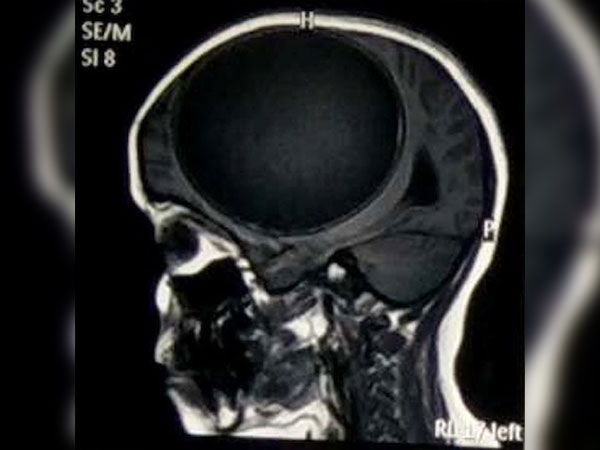

தொடர்ந்து ஆறு மாதங்களாக தலைவலியை குறைக்க முடியாமல் டெல்லிக்கு அருகே உள்ள ஒரு மருத்துவமனைக்கு அழைத்துச் செல்லபபட்டார். மருத்துவரும் சோதித்துப் பார்த்துவிட்டு அதிர்ச்சி அடைந்தார். மூளையில் இருக்கும் வீக்கத்துக்கான காரணத்தை அறிய தலையை ஸ்கேன் செய்து பார்த்தபோது, லீமாவின் மூளைக்குள் நூற்றுக்கணக்கான முட்டைகள் இருந்திருக்கின்றன.

ஒருநாள் தலைவலியால் மயக்கமே அடைந்து விட்டாள் லீமா. மயக்க நிலையில் மருத்துவமனையில் அனுமதிக்கப்பட்ட லீமாவுக்கு சிடி ஸ்கேன் எடுக்கப்பட்டது. அதில் தான் தெரிய வந்தது லீமா நியூரோ சிஸ்டிக் சிரோஸிஸ் (neuro cystic sarcosis) என்ற நோயால் பாதிக்கப்பட்டிருப்பது தெரிய வந்தது.

மயக்க நிலையில் மருத்துவமனைக்கு அழைத்து வரப்பட்ட லீமாவுக்கு உரிய சிகிச்சைகள் கொடுக்கப்பட்டன. அவளுடைய மூளை நரம்பு மண்டலத்தை பரிசோதித்த போது தான் மருத்துவரும் அதிர்ந்து போனார். ஏனெனில் லீமாவின் மூளைக்குள் நூற்றுக்கான வெள்ளை நிறப் புள்ளிகள் இருப்பது கண்டறியப்பட்டது. அது என்னவென்று சோதித்துப் பார்த்தார்கள். அது என்னவென்று தெரியுமா? ஆம் அவ்வளவும் நாடாப் புழுக்களின் முட்டைகள்.

மருத்துவமனைக்கு அழைத்து வரும்போதே லீமாவுக்கு ரத்த அழுத்தமும் அதிகமாகவே இருந்தது. அதனால் மிக கவனமாக மருத்துவர்கள் சிகிச்சை அளித்தனர். நாடாப் புழுக்கள் கொடுத்த அழுத்தமானது மூளையை பாதித்ததோடு மூளையின் செயல்பாட்டையும் நிறுத்திவிட்டது. அதற்காக முதலில் மூளையில் அழுத்தம் குறைவதற்கான மருந்துகள் கொடுக்கப்பட்டன. பின்னர் கட்டி போல இருந்த முட்டைகளைக் கொல்வதற்கு மருந்துகள் கொடுக்கப்பட்டன.